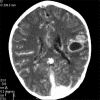

We present two cases of polycythemia secondary to a congenital cardiac anomaly presenting with acute neurological complications showing hyperdense venous sinuses and cerebral vasculature in association with cerebral abscess.